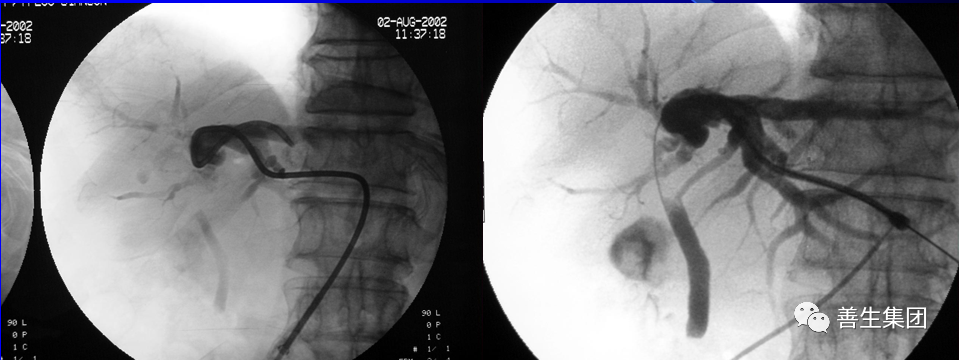

高位梗阻PTC示肝门部梗阻,左右肝管分别受侵犯

高位梗阻胆管癌患者

穿刺右肝管分别穿刺左右肝管,Y型放置2枚支架型内支架